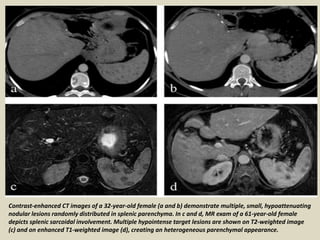

Contrast-enhanced CT images of a 32-year-old female (a and b) demonstrate multiple, small, hypoattenuating

nodular lesions randomly distributed in splenic parenchyma. In c and d, MR exam of a 61-year-old female

depicts splenic sarcoidal involvement. Multiple hypointense target lesions are shown on T2-weighted image

(c) and on enhanced T1-weighted image (d), creating an heterogeneous parenchymal appearance.